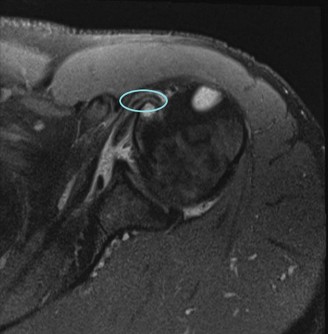

Magnetic Resonance Imaging (MRI), particularly without contrast or as an MR Arthrogram (MRA), remains the gold standard for evaluating the soft tissue envelope of the shoulder. For partial-thickness tears, MRI provides exquisite detail regarding the location (articular-sided, bursal-sided, or interstitial) and the depth of the tear. A T2-weighted coronal oblique sequence will typically demonstrate a focal region of hyperintensity extending partially through the tendon substance. Articular-sided partial tears (PASTA lesions - Partial Articular Sided Tendon Avulsions) are the most common and are best visualized on MRA, where the gadolinium contrast will imbibe into the articular defect, sharply outlining the extent of the avulsion from the footprint.

Should this patient proceed to operative intervention for a high-grade articular-sided partial tear (PASTA lesion), the procedure is performed entirely arthroscopically. The patient is positioned in either the beach chair or lateral decubitus position, depending on surgeon preference. A standard posterior viewing portal is established, and a thorough 15-point diagnostic arthroscopy of the glenohumeral joint is performed. The articular surface of the supraspinatus is meticulously inspected. The partial tear will appear as a region of avulsed, frayed tendon fibers lifted off the medial aspect of the greater tuberosity footprint.

To accurately gauge the depth of the tear, a calibrated probe is used. If the tear is deemed to involve greater than 50% of the footprint (typically exposing more than 6-7 mm of bare bone medial to lateral), a repair is indicated. The footprint is first debrided using a motorized shaver and an arthroscopic radiofrequency wand to remove degenerative tissue and expose a bleeding cancellous bone bed, which is critical for optimal tendon-to-bone healing.